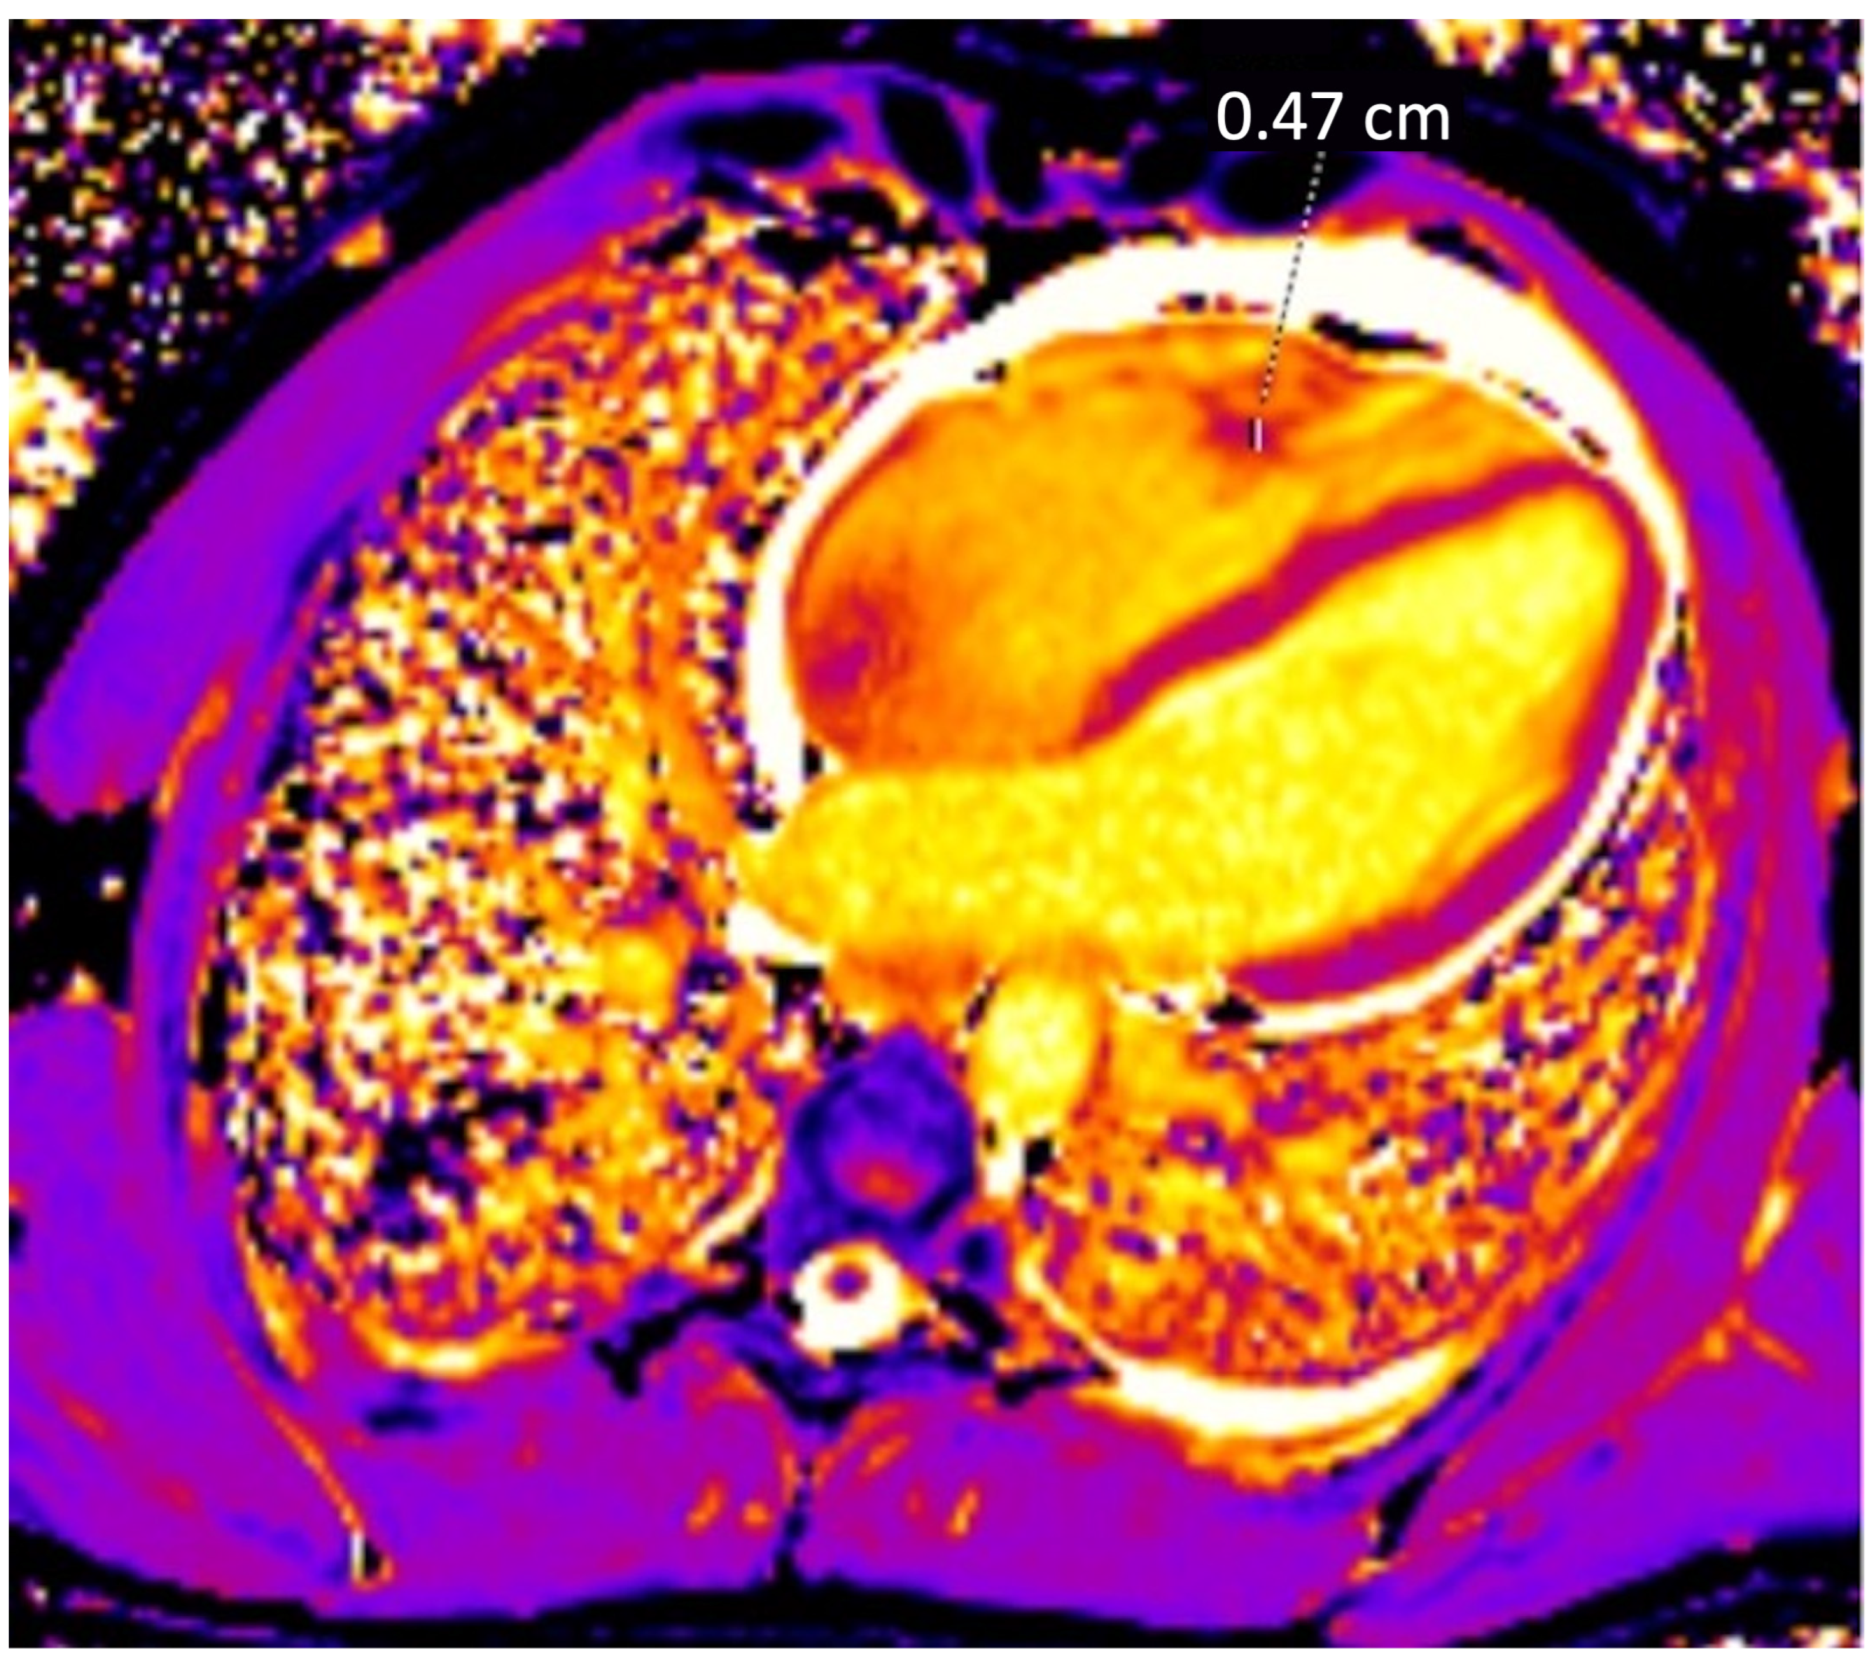

During investigation, a murmur was heard during heart auscultation, and echocardiography showed vegetations on the mitral and bicuspid valves. Further, an MRI and transesophageal echocardiography were performed. These revealed a pulmonary embolism as well as an intracardiac thrombus of 4.7 mm in diameter (Figure 2). Using computer tomography, splenomegaly and suspected infarction of the right kidney were ascertained.

Figure 2.

MRI of the heart visualizing a thrombus in the right ventricle.